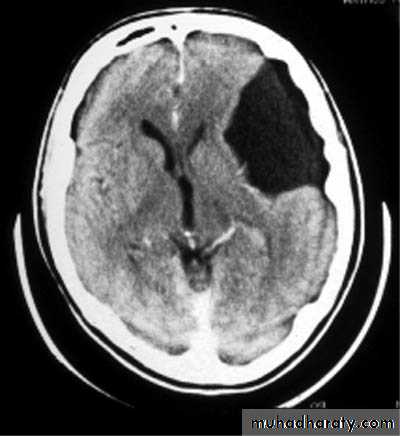

Sylvian Fissure Arachnoid Cyst

Developmental Abnormalities of the Nervous System